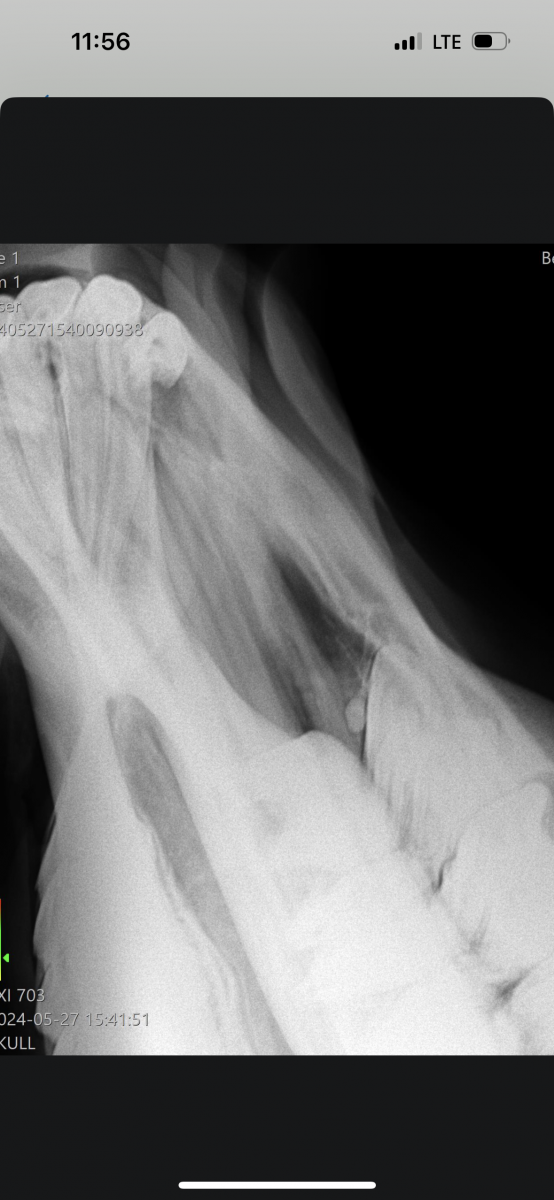

Далее сделали рентген (прилагаю его), врач заподозрил может киста, во рту ничего не нашли (думали на зуб), корни зубов хорошие, десна все тоже.